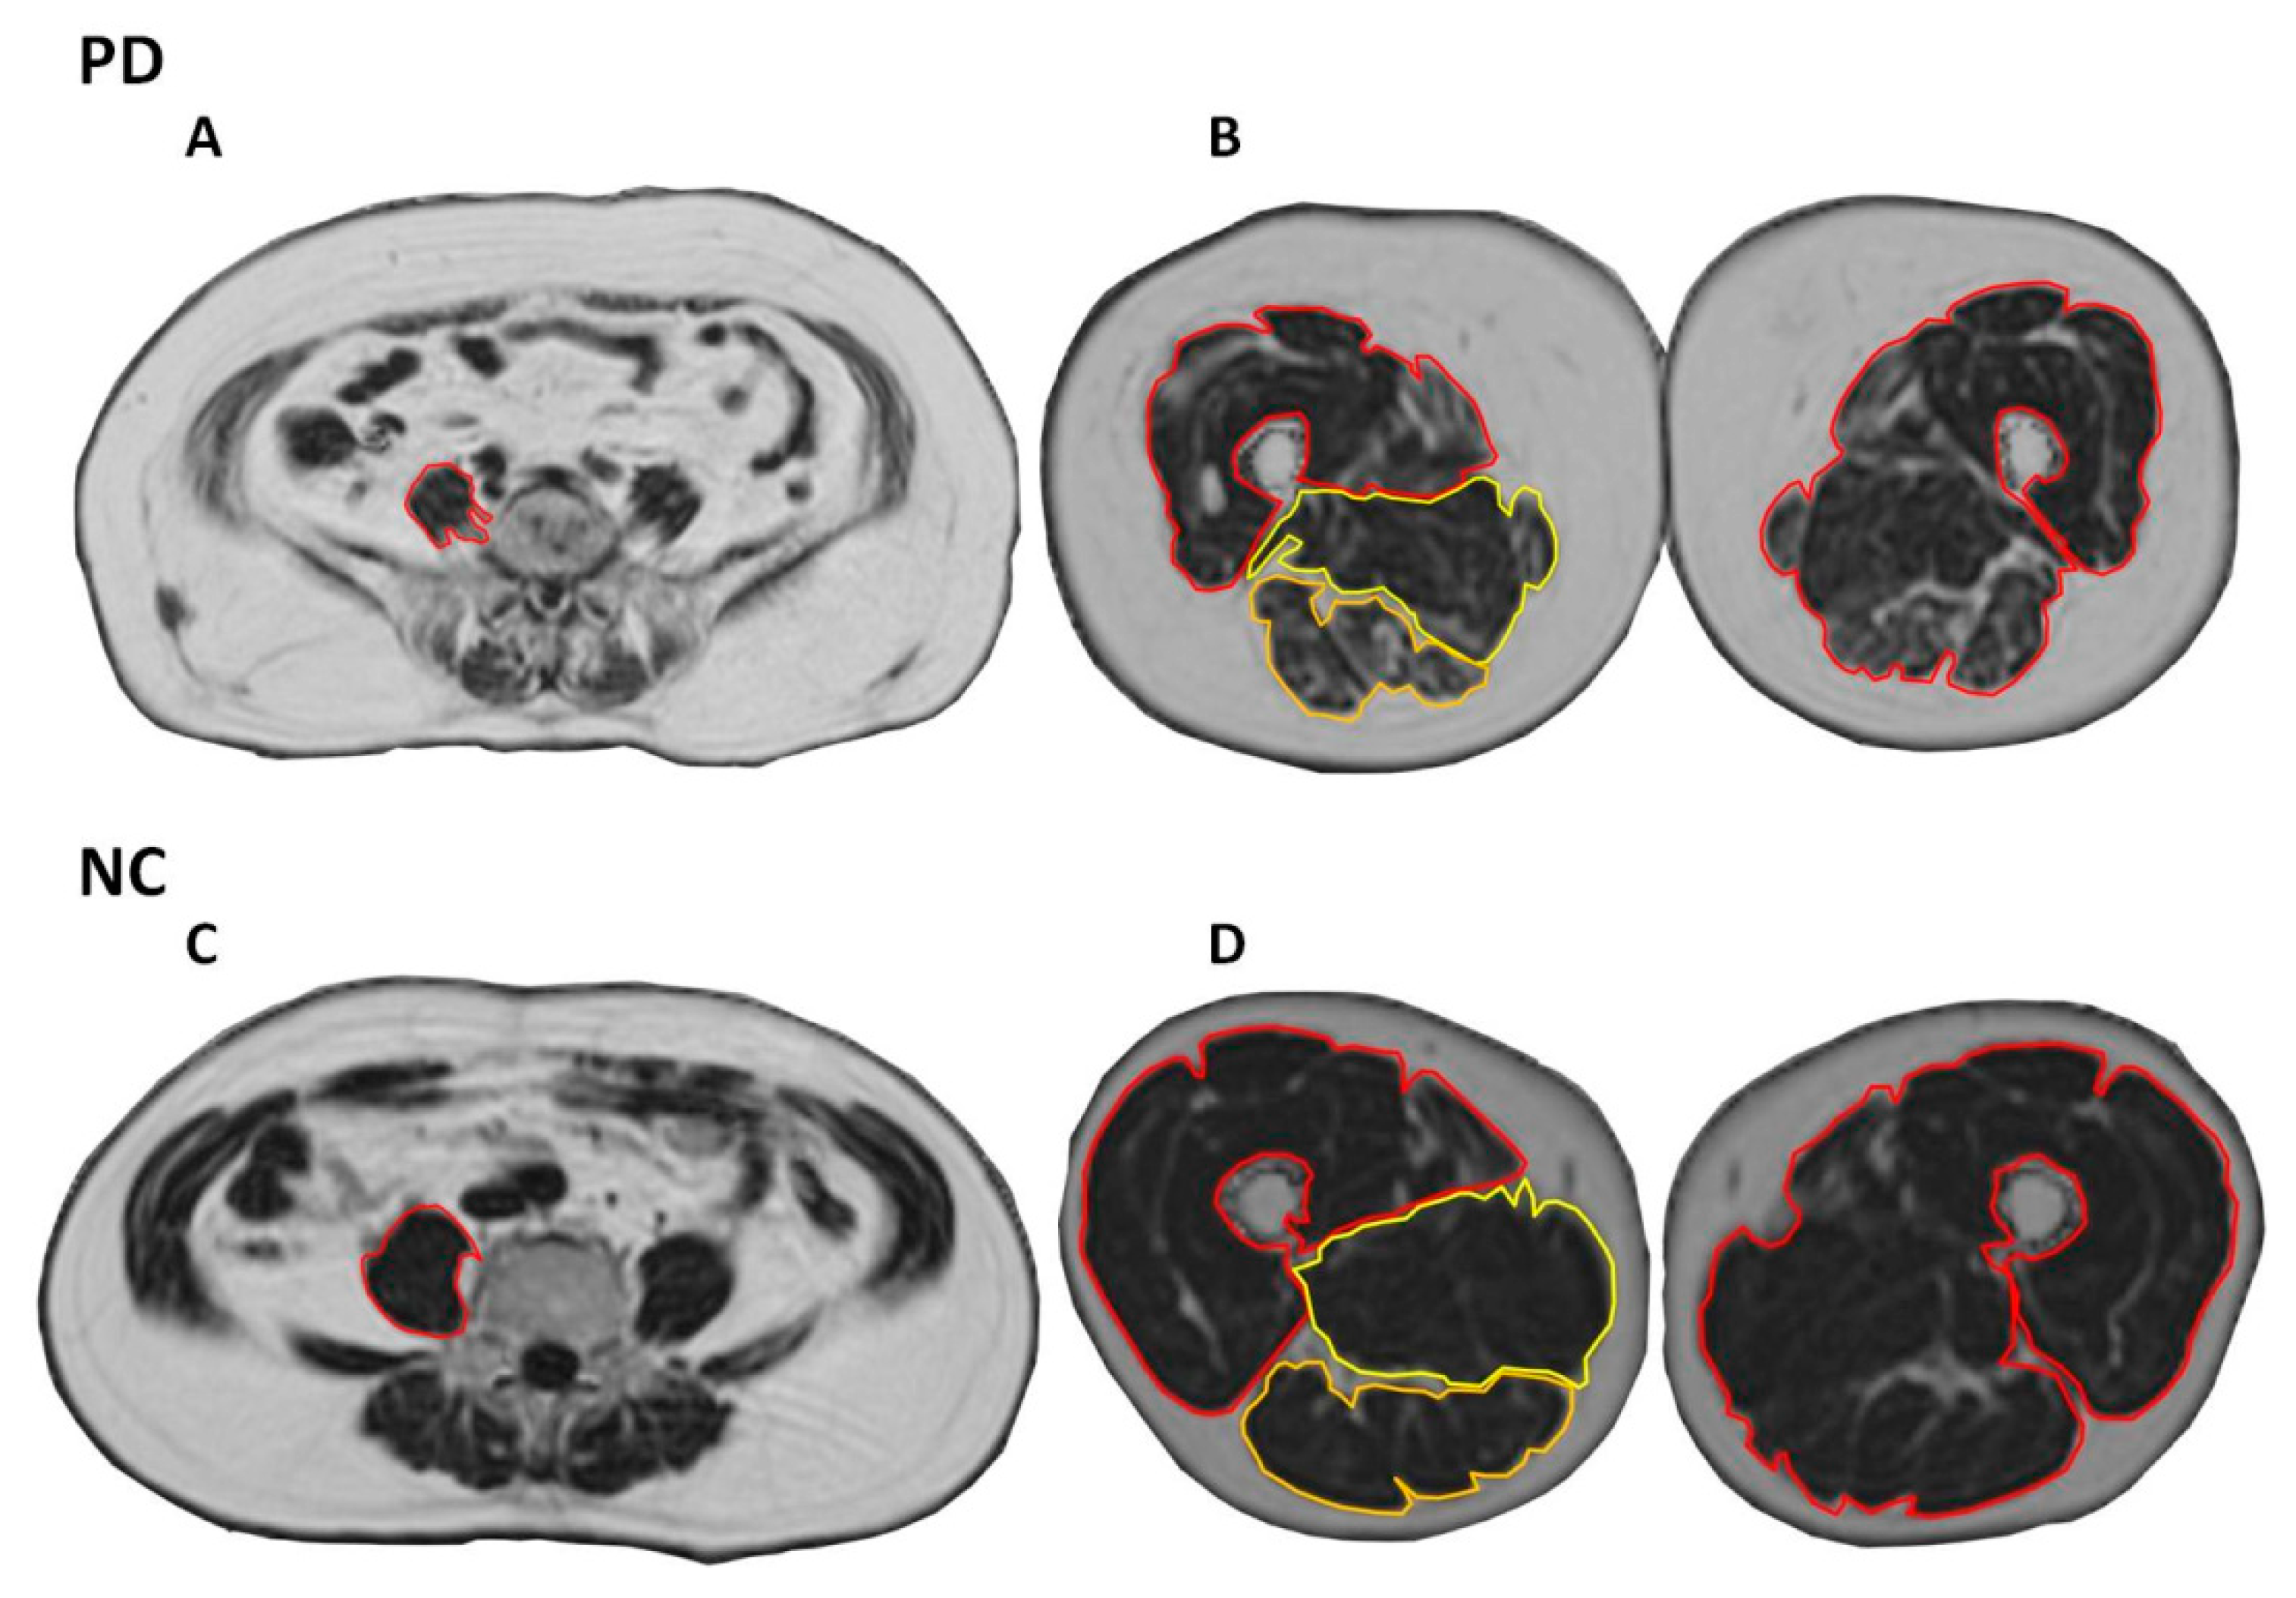

2.5. Regions of Interest (ROI)

2.6. Assessment of Cross-Sectional Area